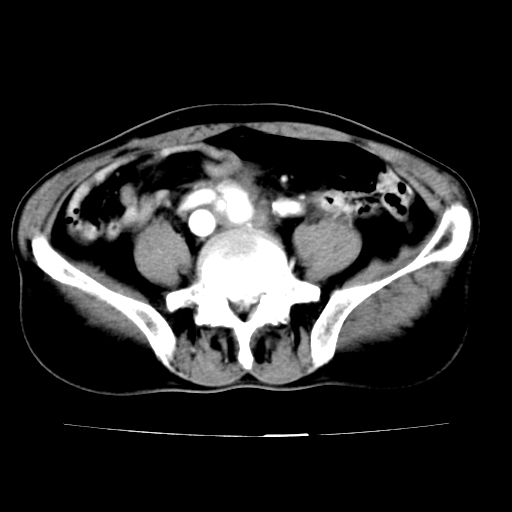

标题: V0243:右髂总动脉瘤附壁血栓形成?破裂?动静脉瘘? [打印本页]

标题: V0243:右髂总动脉瘤附壁血栓形成?破裂?动静脉瘘?

男,75岁,腹痛月余,彩超发现脐周腹主动脉异常回声。临床诊断:腹主动脉瘤。

ct诊断:右骼总动脉囊性动脉瘤并瘤内附壁血栓形成,与下腔静脉之间形成动静脉瘘。

请问各位老师:能排除动脉瘤破裂的可能吗?

各位老师注意到下腔静脉的充盈缺损了吗?注意到动静脉漏了吗?

当时是扫描的标准动脉期,可是下腔静脉与腹主动脉同步强化且幅度一致。所以我想动静脉瘘是存在的。